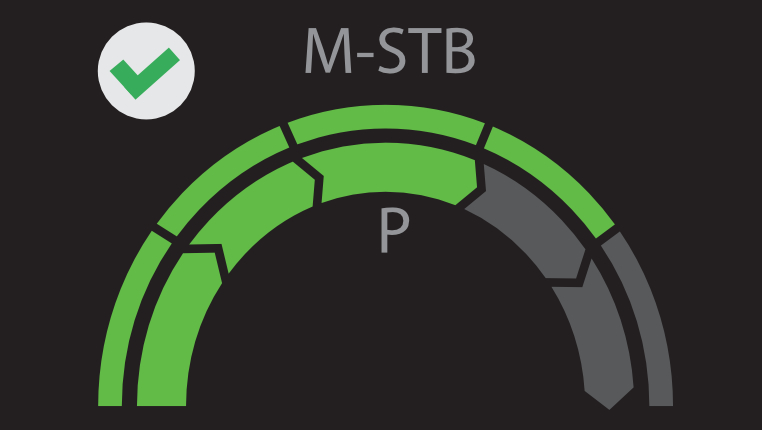

? ??? ?? ???? ???? ?? ???? Hepatus? ? ??? ??? ???? ??? ??? ?????. ???? ????? ??? ? ?? ??? ???? ????? ? ?? ???? ? ?? ??? ??? ??? ?????.

??? ???? ?? ? ??? ? ? ???? ?? ??, ??, ???? ? ?? ??? ??? ? ????. ?? ?? ???? ?????.